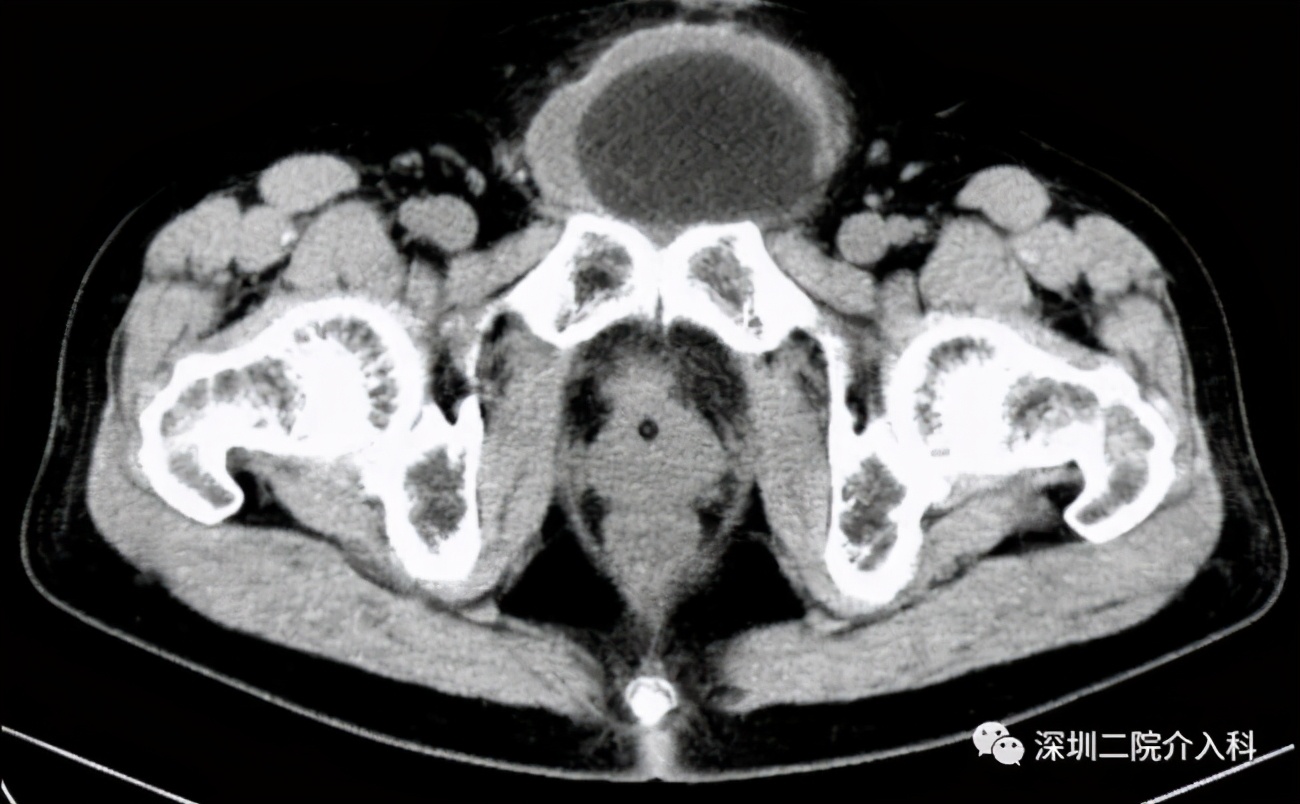

图示复查CT见冰球范围内肿瘤组织彻底坏死: